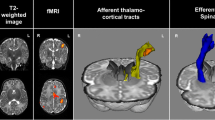

Processing steps are identical to our previously published work and are outlined in Fig. 15. Anatomical T1 images underwent preparation for anatomically constrained tractography (ACT)17. Due to the heterogenous nature of the size and location of perinatal strokes, multiple software packages were used to optimize the preprocessing and analysis pipelines. T1 scans were parcellated into gray matter, white matter, cerebrospinal fluid, bone, and air using the Statistical Parametric Mapping segmentation tool (https://www.fil.ion.ucl.ac.uk/spm/). To permit reconstructed streamlines to pass through subcortical motor structures (e.g., thalamus), we isolated subcortical structures using FMRIB Software Library (FSL)’s FIRST, then removed these structures from the termination processing within ACT18. Once all segmentations were completed, the interface between gray and white matter was generated and this image served as both the initial tractography seed and termination point to constrain reconstructed streamlines to only white matter17.

Neuroimage processing steps. (A) Anatomical images were segmented based on tissue type and combined to create a gray matter-white matter interface (GMWMI) image. The AAL2 atlas (node atlas) was co-registered into patient diffusion space. For DTI images, eddy currents and small head motion was corrected. ODF maps were then generated and whole-brain tracts were reconstructed (restricted to only white matter using the GMWMI image) and seeded using the co-registered node atlas to generate an undirected 47 × 47 node adjacency matrix containing number of streamlines between node pairs (network weights). Network weights in the non-lesioned hemispheres were compared between groups of children with perinatal stroke (AIS, PVI) and the left hemisphere in controls. Asterisks highlight steps where quality assurance was performed by two authors. (B) Group average adjacency matrices for AIS, PVI and TDC participants as well as matrices containing standard deviations to visually illustrate variances between the groups. Images in (A) were generated using MRTrix3 (https://www.mrtrix.org/) and images in (B) were generated using MATLAB (https://www.mathworks.com/products/matlab.html). DTI diffusion tensor image, ODF orientation density function, AIS arterial ischemic stroke, PVI periventricular venous infarction, TDC typically developing controls.